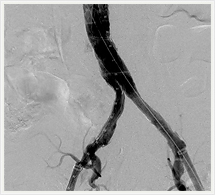

画像紹介(ステントグラフト編)

ステントグラフトは、人体に馴染みやすい人工布を筒状に形成し、これにステントといわれるバネ状の金属を縫い付けた人工血管で、これをストロー状のチューブで、患者さんの太ももの付け根から動脈内に挿入します。ステントグラフトを動脈瘤のある部位まで進め動脈瘤の内側ステントグラフトを挿入します。そうすることで動脈瘤の拡大を抑え、動脈瘤が拡大しなければ破裂する危険性がなくなります。このように、ステントグラフトによる治療は外科手術に比べて切開部が小さく、身体への負担が極めて少ない低侵襲血管内治療です。

ステントグラフト挿入術直後の造影

(上部)

(下部)